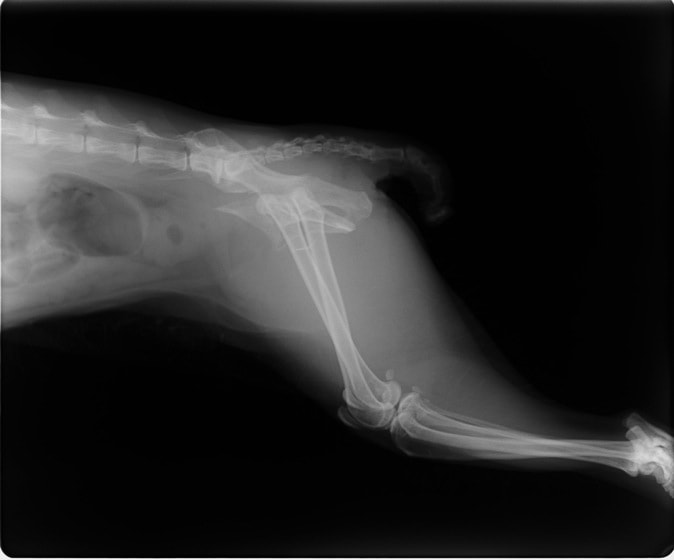

ペルシャ猫 11ヶ月齢 雄

他院にて左大腿骨遠位の成長板骨折(salter-harrisⅠ型)が認められており、治療相談を目的として来院。当院にて、キルシュナーワイヤーを用いたピンニングにより骨折部位の整復を行いました。術後の経過は良好で、現在も経過観察中です。

術前レントゲン